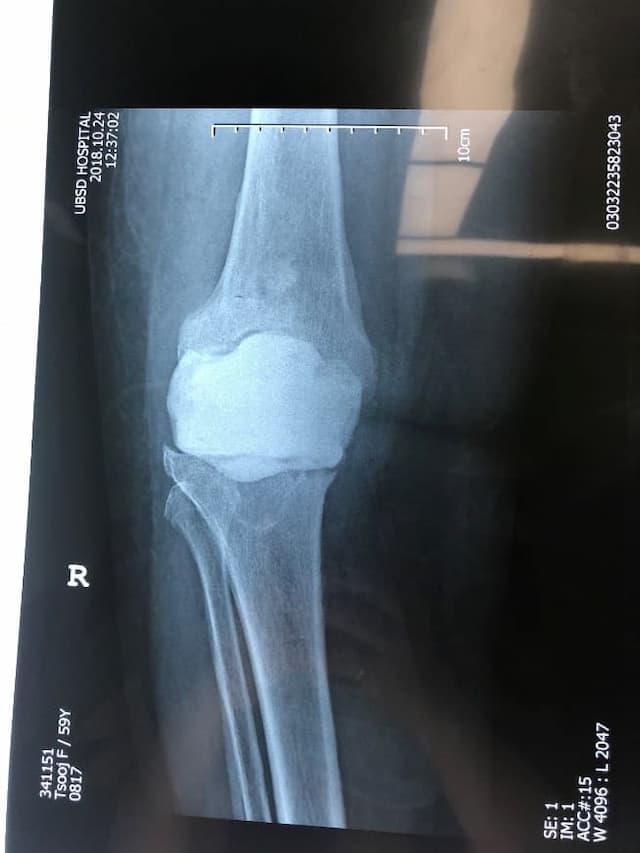

Үе дайрсан ясны анхдагч хавдар, ясны дутмагшлын үед хийгдэх мэс засалimg27Үе дайрсан ясны анхдагч хавдар, ясны дутмагшлын үед хийгдэх мэс засалimg28

Зураг 1. Сэргээн засах мэс заслын өмнөх рентген зураг. Эгц урд, хажуугаас авсан байдал. Халдварын бус шалтгаант хиймэл үений ховхрол.